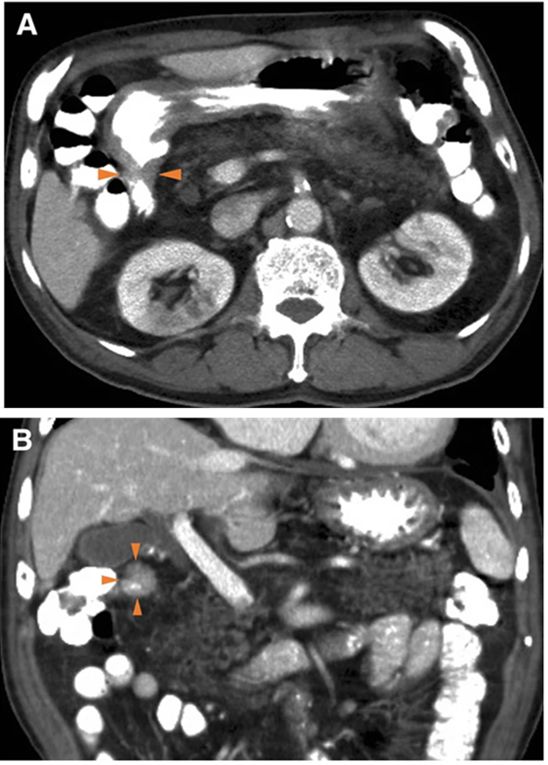

多层螺旋CT增强扫描可显示十二指肠球部管壁厚度,未发现淋巴结肿大(图2)。黏膜下肿瘤样病变活检标本未显示恶性肿瘤的证据。由于临床上尚不能排除恶性肿瘤的可能性,故拟行手术切除肿块,以诊断和治疗该疾病。

图2 多层螺旋CT增强扫描显示十二指肠横断面(A)和冠状面(B)管壁厚度。箭头:十二指肠球部管壁厚度